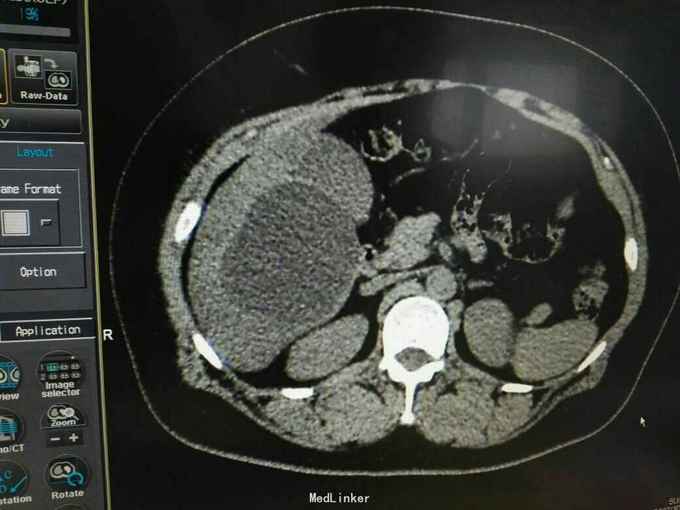

巨大肝囊肿

发现肝脏占位10年

肋弓下可触及囊性占位

肝囊肿

今日在局麻下行囊肿穿刺抽吸+无水酒精注射术 术中共抽取淡黄色液250ml